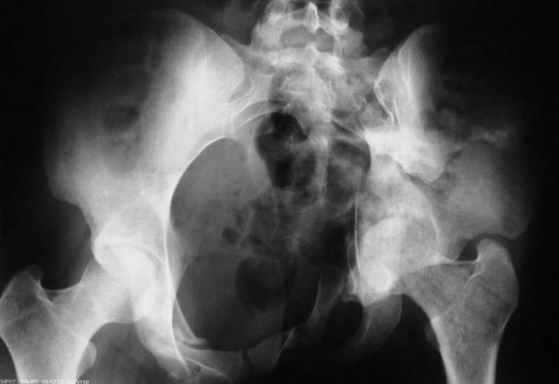

В заключении будет демонстрация операции больной 27 лет с давностью травмы более 2,5 мес.(3D прилагается) Убедительная просьба до 24.11.2008 всем желающим сообщить по адресу: pelvistrauma@mail.ru следующие данные: 1. Ф.И.О. 2. Должность и место работы 3. Контактный телефон. Семинар состоится на базе ГКБ №15 по адресу: г.Москва, ул. Вешняковская, д.23. административный корпус, IV этаж, 1 травматологическое отделение

Уважаемый коллега, не стоит строить утвердительные предложения с выражением "Вам не кажется". Данный хирургический доступ применяется около 8 лет. Помимо того что создаются благоприятные условия для репозиции, сокращается время операции и как следствие - уменьшается кровопотеря, которая составляет около 1 л. при свежих случаях. При застарелых же, по очевидным причинам, существенно выше. Максимальная кровопотеря была 5450 мл. у больного после спленэктомии и давностью травмы более 1 года. Была выполнена одномоментная реконструкция таза с протезированием тазобедренного сустава. Пользуемся Cell Server-ом, производим аутозабор в предоперационном периоде, возвращаем дренажную кровь. ДВС? Тьфу, тьфу, тьфу! Это заслуга АРО и трансфузиологов, и именно они нам позволяют выполнять такие вмешательства.

На счет оправданности можно почитать на форуме http://weborto.net/forum/1228932999/index_html Антибиотики - цефалоспорины III поколения. Первая доза - интраоперационно. Продолжительность операции от 1,5 до 6 часов. К сожалению больная была выписана на 11-ые сутки. Представляю послеоперационную рану пациентки с аналогичной травмой и операцией, которая явилась на плановую консультацию через 3 мес.

Ни одного случая нарушения функций тазовых органов. Ни одного случая эректильной дисфункции. А по поводу стрессового недержания мочи - все гораздо проще: если не оперировать, а точнее не восстанавливать переднее полукольцо данный недуг не всегда удается излечить урологам, даже после многочисленных пластических операций. Кстати, в мае этого года на Пироговской конференции об урологических аспектах... докладывал А.Ф.Лазарев. Другое дело - нейропатия малоберцового нерва. К сожалению мы с этим сталкиваемся достаточно часто, когда одномоментно приходится низводить гемипелвис на 5 и более см. Наверное, это неизбежно. На фоне реабилитации обычно нерв восстанавливаются в течение одного года.